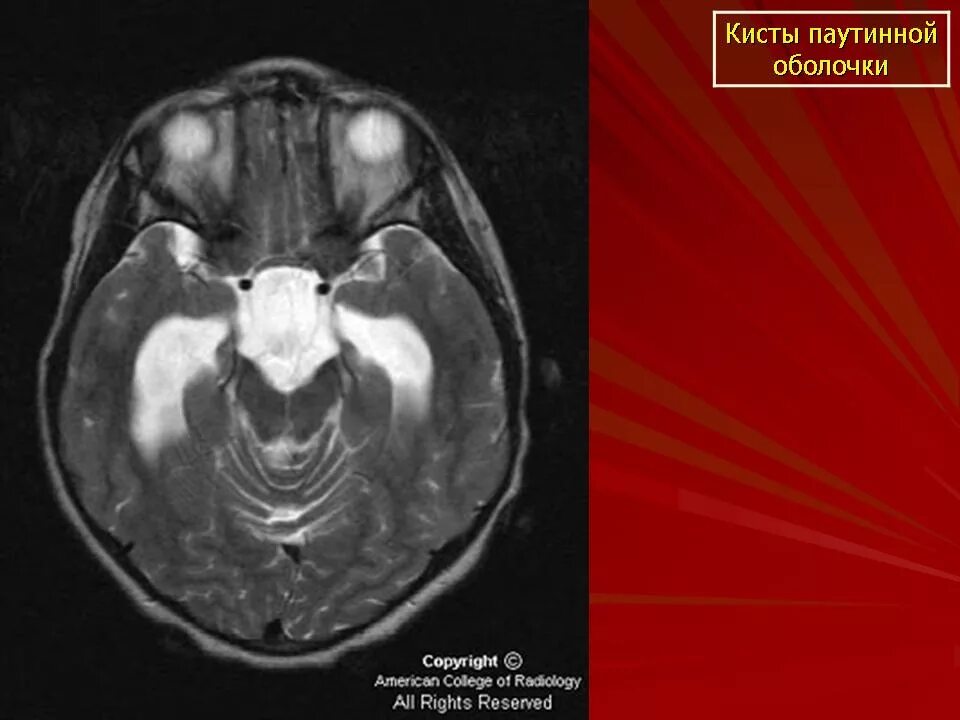

Кисты в голове форумАксиальная дислокация головного мозга. киста в голове у взрослого размеры нормы.Кисты в голове форумКисты в голове форумКисты в голове форумКисты в голове форумКисты в голове форумКисты в голове форумКисты в голове форумФенестрация кисты головного мозга.Кисты в голове форумЛакунарная киста головного мозга на кт. киста в голове у подростка.Как выглядит киста в голове. кист болит от нагрузки.Кисты в голове форумКисты в голове форумКисты в голове форумКисты в голове форумАрахноидальная киста в голове у ребенка. арахноидальная киста у плода.Кисты в голове форумКисты в голове форумПаренхиматозная киста головного мозга. микроскопическое строение кисты головного мозга. посттравматическая киста головного мозга кт. множественные кисты в головном мозге.Самая большая киста в голове. киста в голове у подростка.Кисты в голове форумКисты в голове форумКисты в голове форумКисты в голове форумКисты в голове форумКисты в голове форумКисты в голове форумКисты в голове форумКисты в голове форумКисты в голове форумКисты в голове форумКисты в голове форумКисты в голове форумКисты в голове форумКиста головного мозга у новорожденного. киста в голове у новорожденных. киста в головном мозге у новорожденных.Кисты в голове форумЛекарство от кисты головного мозга. таблетки от кисты в голове.Кисты в голове форум